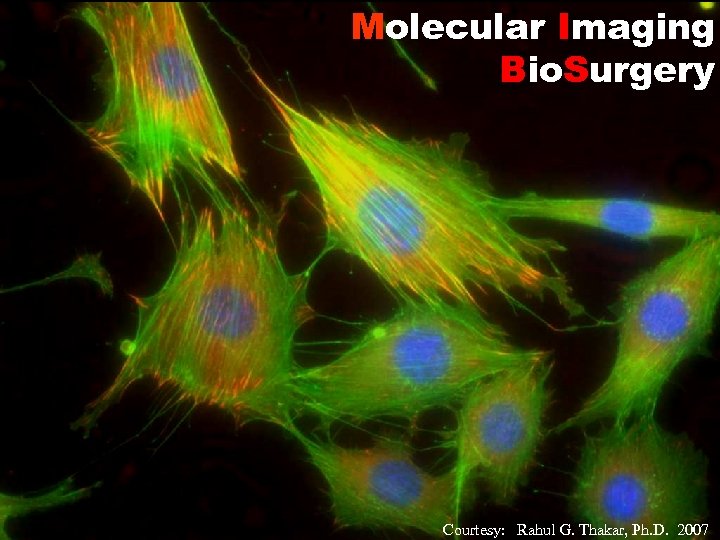

Molecular Imaging Bio. Surgery Courtesy: Rahul G. Thakar, Ph. D. 2007

Molecular Imaging Bio. Surgery Courtesy: Rahul G. Thakar, Ph. D. 2007